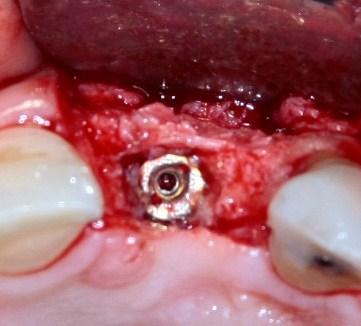

Например, в следующей ситуации:

Оставить так, как есть — это значит, сильно рисковать имплантом и объемом альвеолярного гребня — фактически, большая часть импланта пятого зуба «висит в воздухе». Поэтому получившуюся костную полость мы заполняем аутокостной стружкой в смеси с Bioss и закрываем коллагеновой мембраной BioGide:

При необходимости, мембрану можно фиксировать пинами.

Через три месяца результат:

можно ставить формирователи и заканчивать лечение:

В указанном выше случае использование костных блоков просто невозможно.